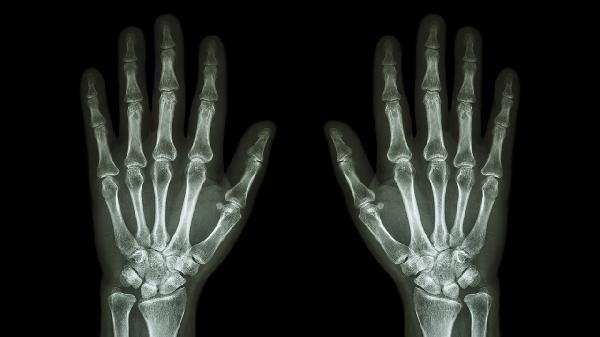

手指关节可能出现腱鞘炎,主要表现为局部疼痛、活动受限等症状。腱鞘炎通常由过度使用、外伤、感染、风湿性疾病、代谢异常等因素引起,可通过休息制动、药物治疗、物理治疗、局部封闭、手术松解等方式缓解。